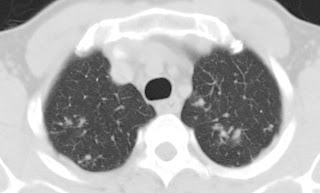

50 year-old man presented with an intramedullary tuberculoma of the thoracic spinal cord manifesting as a 2-month history of progressive paraparesis and sphincter dysfunction. Magnetic resonance imaging showed ring enhancement of the intramedullary thoracic lesion with perifocal edema. CT chest was done and revealed apical infiltrates.